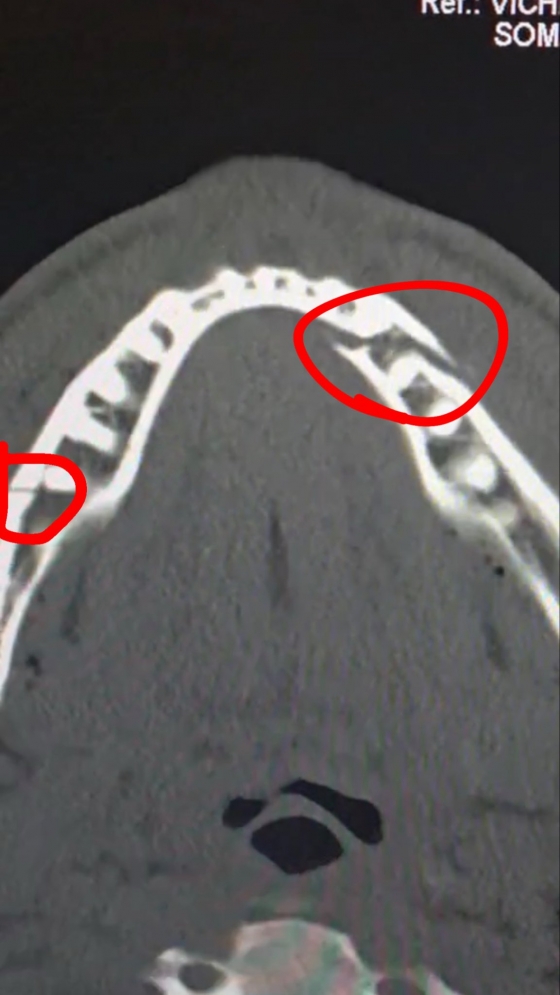

但是在第6轮1分31秒左右,约书亚强有力的右手直拳击中了保罗的下巴,保罗的下巴骨折了两处,比赛就这样结束了。

赛后经过仔细检查,保罗的情况比预想的要严重得多。 保罗立即被送往医院,接受了插入4个钛板固定颌骨,并去除部分牙齿的大手术。

保罗在接受体育专门频道"DAZN"采访时表示,"下巴上钉了四个板子。 恢复过程太辛苦了。"